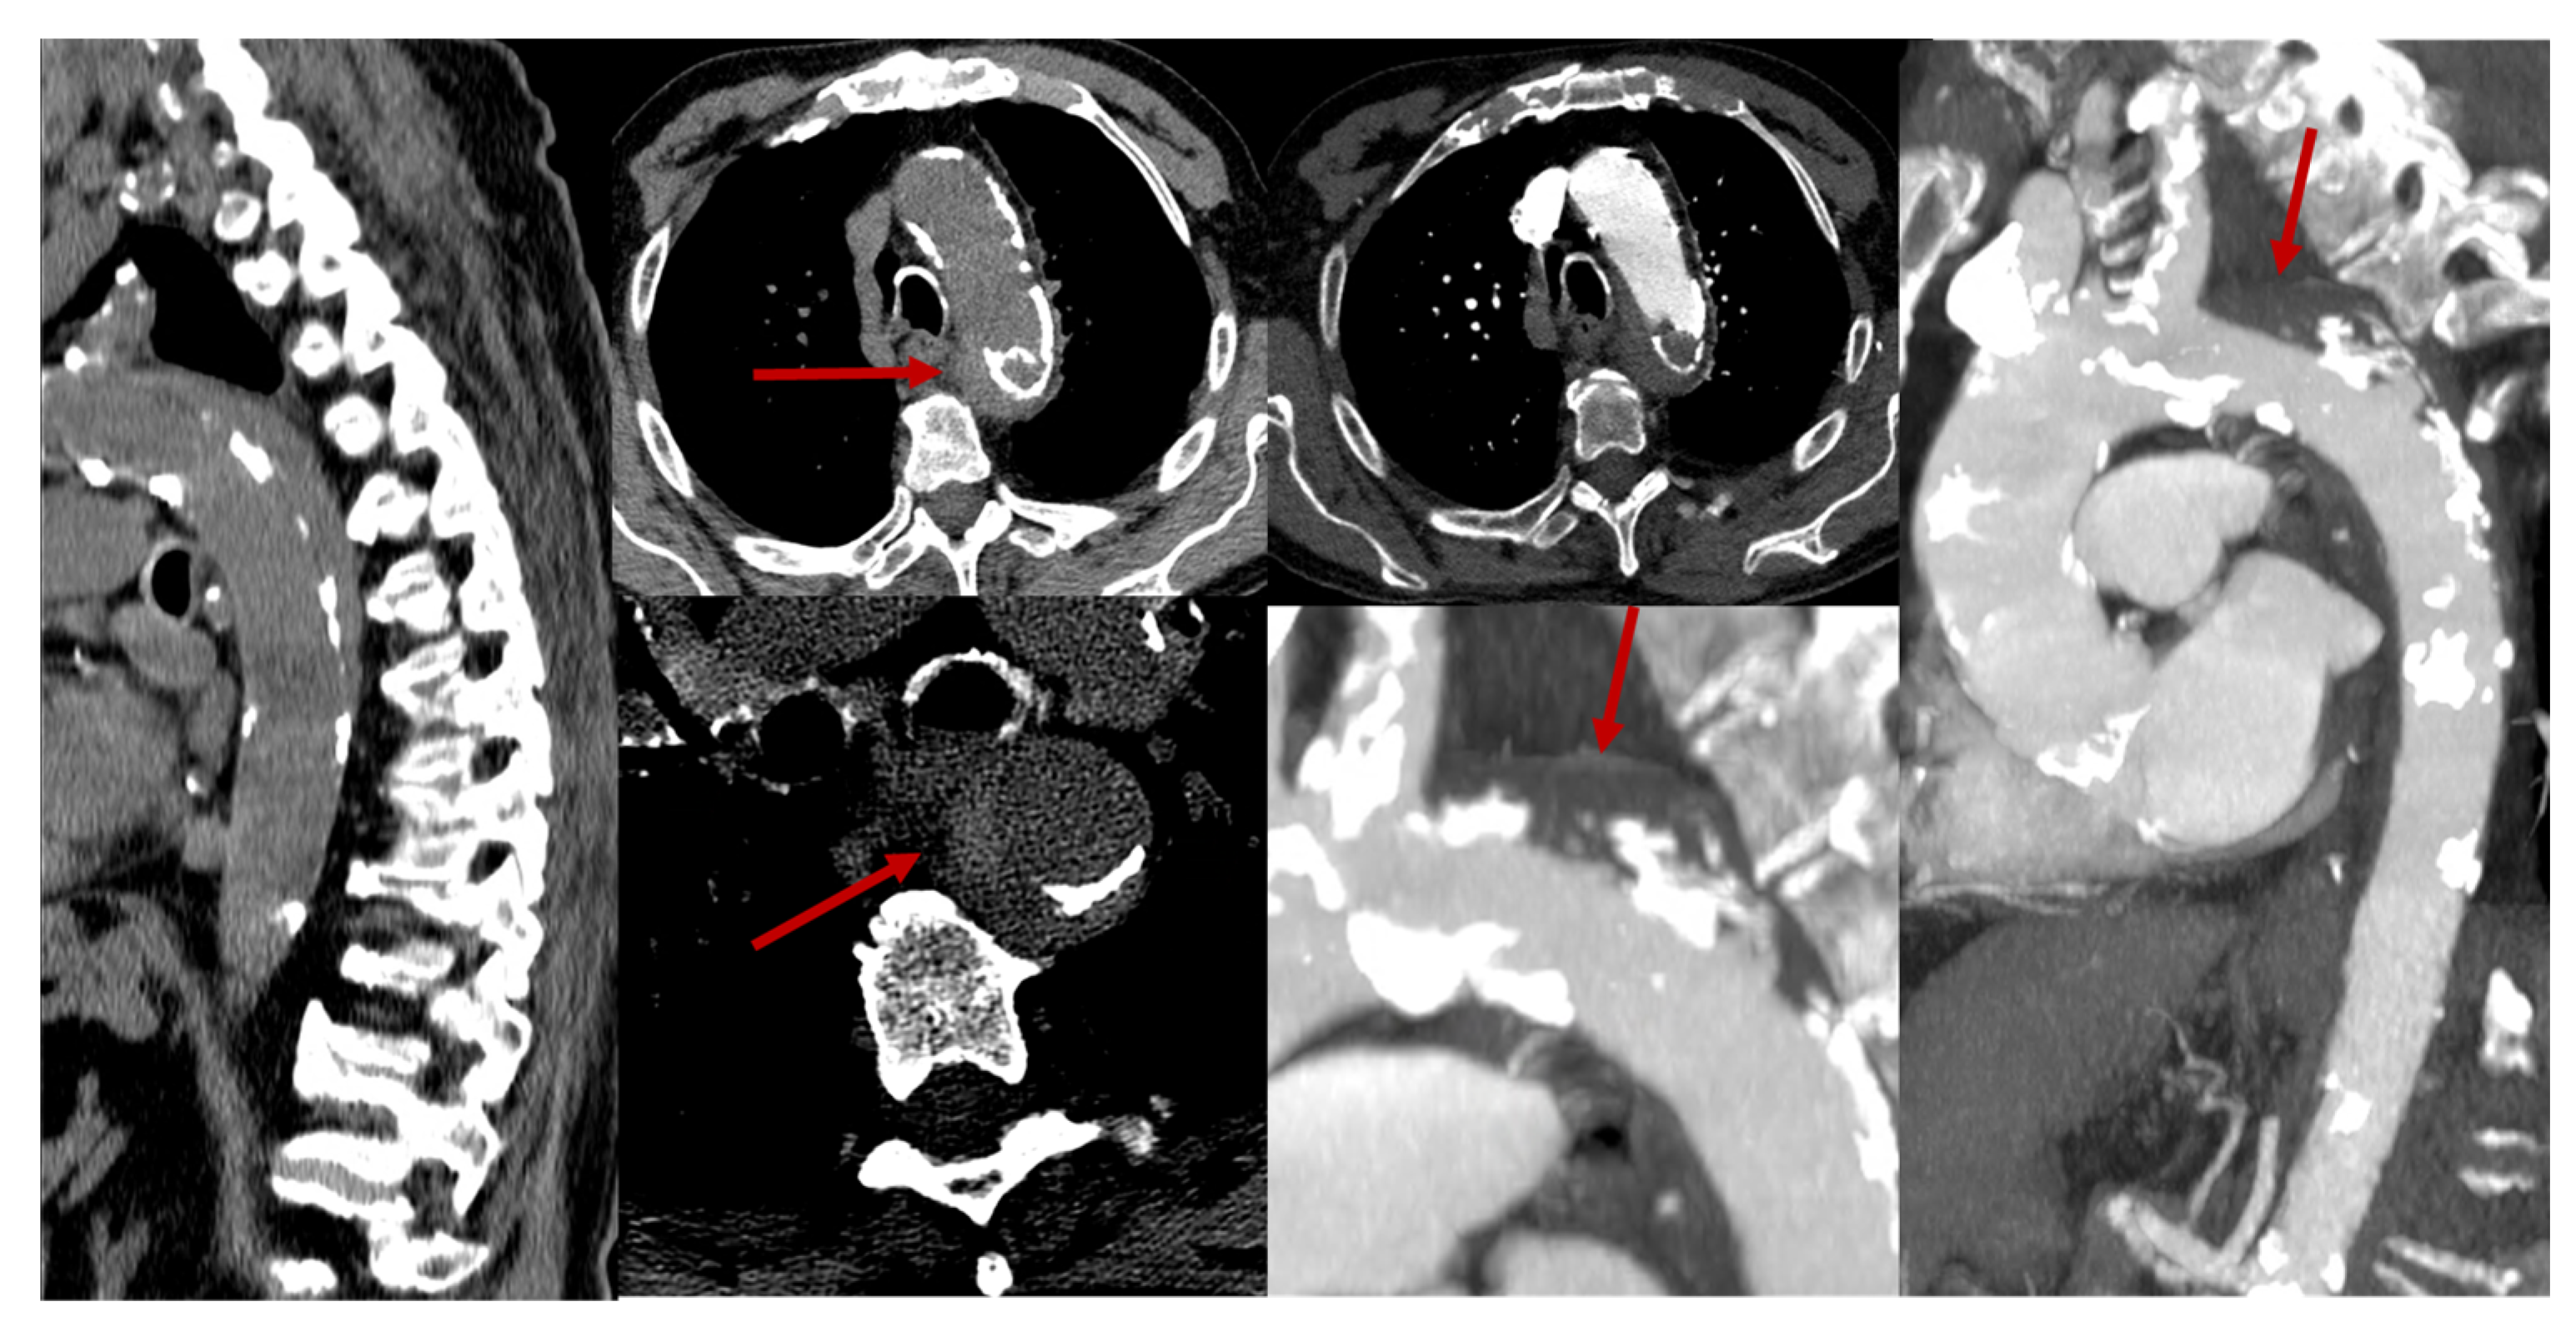

- Vertebral body infarcts may also be observed.